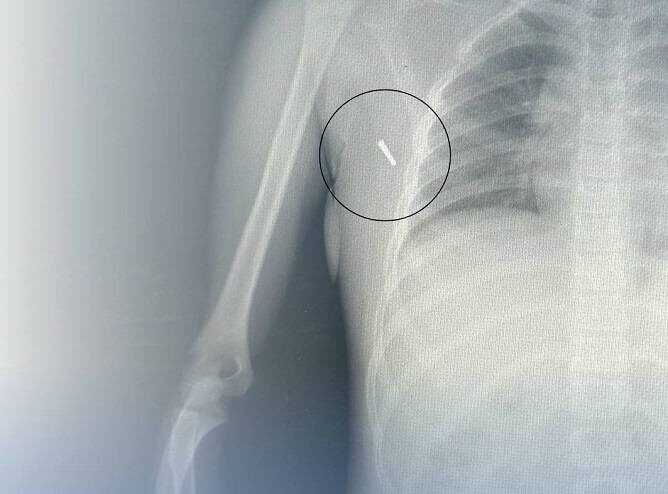

Часть градусника извлекли из тела девочки врачи в Артеме

Врачи стационара извлекли часть градусника из подмышечной впадины 8-летнего ребенка, пострадавшего в ДТП, сообщают «Вести:Приморье».

18 июля в вечернее время в приемное отделение стационара поступила 8-летняя девочка с травмой. Во время поездки на автомобиле у ребенка был установлен ртутный градусник для измерения температуры тела. В результате ДТП наконечник градусника отломился и вонзился в подмышечную впадину ребенка.

Специалисты отметили, что основной опасностью являются пары ртути, которые выделяются при вдыхании в случае разбивания градусника. Важно подчеркнуть, что само вещество ртути, попадающее в организм в минимальных количествах, не представляет серьезной угрозы. Таким образом, хирургическое удаление наконечника можно провести безопасно.

Наши травматологи успешно извлекли наконечник, провели контрольные анализы и рентген-снимок после изъятия, а затем оставили девочку на несколько дней в стационаре для наблюдения.

Сейчас девочка чувствует себя хорошо и уже выписана домой.